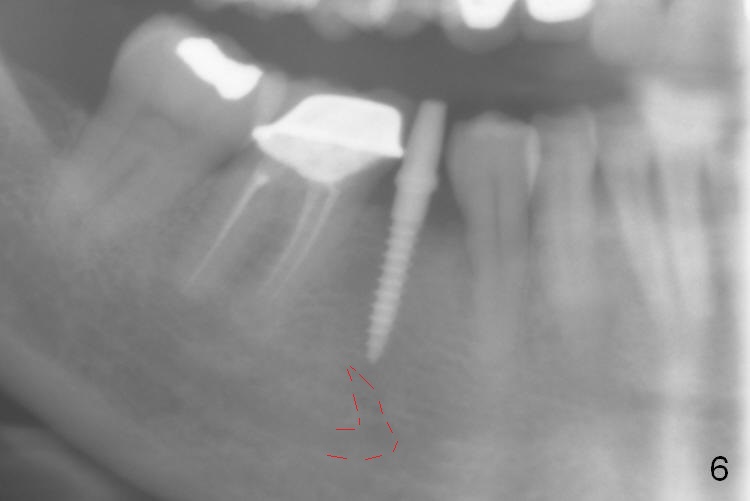

Preop photo shows the distal inclination of the tooth #28 (Fig.1).  The distal surface of the latter is reduced before incision for implant placement at #29 (Fig.2).  The buccolingual width is approximately 4 mm, as compared to 3 mm implant positioner (Fig.3).  After 1.2x10 mm osteotomy (Fig.5), the mesiodistal cortical bone is removed with a small high-speed fissural bur (Fig.4).  When a 2.5x12(2) mm 1-piece implant is placed (Fig.6), there is no buccal (Fig.7) or lingual plate perforation.  There is no postop paresthesia.  There is mild bone loss distal 4 months postop (Fig.8 *).  Take photos before and after permanent crown cementation to show increase in ridge width after bone graft and improvement in gingival health after provisional modification.  Take PA and/or BW post cementation to show that the distal bone resorption (Fig.8 *) is partially due to angulation.  No continuous bone loss 15 months post cementation (Fig.9).  There is mild bone resorption mesially 2 years 3 months post cementation (Fig.10).  The soft and hard tissues remain healthy 4 years 3 months post cementation (Fig.11,12).